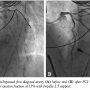

placed. Baseline cardiac output and capillary wedge pressure were 4.5 L/min and 25 mm Hg, respectively. Two minutes after placement of the Impella 2.5, these parameters improved to 6.0 L/min and 18 mm Hg, respectively and systemic blood pressure as measured in the proximal aorta improved to 110-120/55-70 mm Hg. The 90% proximal stenosis of the first diagonal artery was then successfully treated by PCI with a 2.5 x 28 mm drug-eluting stent (Figure 1B). Subsequently, a spiral left main (LM) guide dissection was identified (Figure 2). The patient remained hemodynamically stable. The protected left anterior descending (LAD) artery and unprotected diagonal were wired and PCI from the diagonal artery into the proximal LAD and the LM with 2.5 x 28 mm and 3.5 x 15 mm stents was successfully undertaken (Figure 3). The aortic valve was then crossed with a second wire and successful BAV with a 20 x 6 mm Z-Med II Balloon (NuMED, Inc) was performed (Figure 4). Rapid pacing of the right ventricle was not necessary. The patient remained hemodynamically stable throughout the whole procedure. The Impella was left in for 24 hours before being weaned and removed. The patient was discharged on home inotropes. At 6-week follow-up exam in the heart transplant clinic, he remained stable with NYHA III symptoms and was listed for heart transplant as a United Network of Organ Sharing (UNOS) Status IB. At 8 weeks, he underwent successful heart transplant surgery.